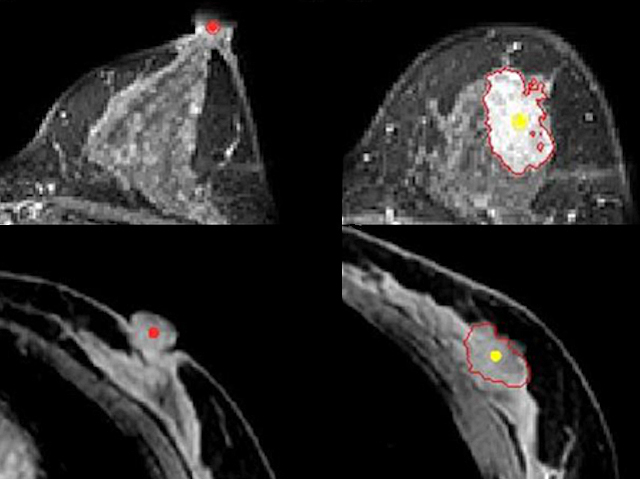

Pinpointing Breast Cancer

Comparing supine and prone breast scans using computer algorithms to ensure tumours accurately pinpointed in surgery

Surgery is the single most effective treatment for breast cancer diagnosed at an early stage, before it has spread through the body. If the tumour is small enough, patients will be offered a ‘lumpectomy’ (breast conserving surgery) rather than removing the whole breast. In order to cut out the tumour and a safe margin of healthy tissue around it, which may be harbouring rogue cancer cells, it’s essential that the surgeon knows exactly where it is within the breast. This is usually done through an MRI scan, with the patient lying face down inside the scanner. However, surgery obviously has to be done with the patient lying face up. Researchers are using computer algorithms to analyse and compare MRI scans taken in the face down (top row) or face up position (bottom row), enabling surgeons to predict the location of a tumour more accurately and ensure they’ve removed it all.